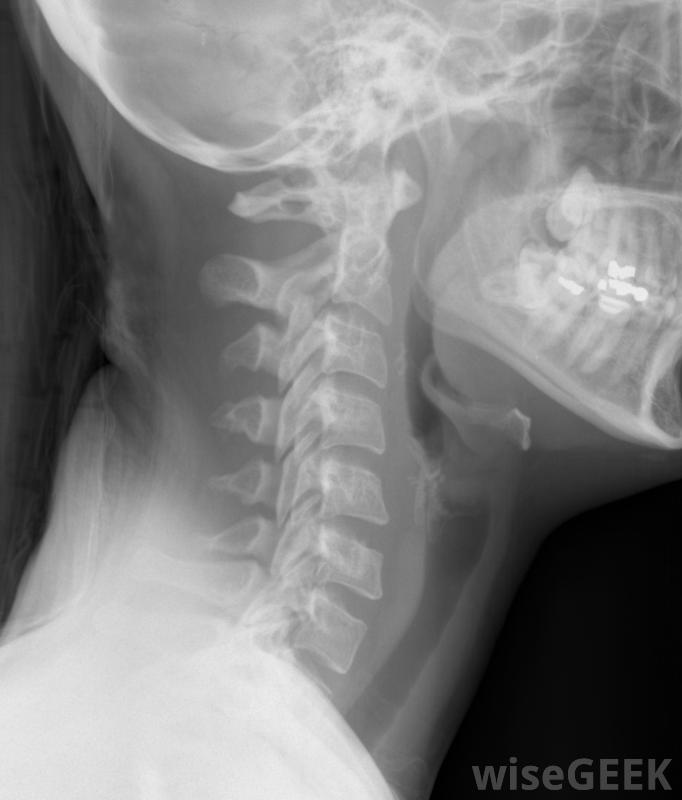

什么是頸椎融合(Cervical Spine Fusion)?

當頸椎或頸部持續疼痛無法用其他方法成功治療時,有時需要進行頸椎融合。這種手術將頸部的椎骨相互融合,限制運動,從而減輕或消除疼痛。有時,頸椎融合術是結束長期疼痛的最佳方法頸椎的慢性疼痛通常是由神經壓迫引起的,在神經受壓處融合椎體,可大大減少該區域的活動,也有助于為神經和神經根留出額外的空間,其結果是減輕受影響神經的壓力,這樣可以減輕甚至消除疼痛。大多數人在頸椎融合術后的恢復過程中都會戴上頸領頸椎融合術也可以在頸部受傷后進行,以防止脊椎骨折對脊髓的損害,也可以幫助矯正脊柱錯位或畸形,或治療由類風濕性關節炎或其他慢性病在某些情況下,頸椎融合術是為了跟進椎間盤突出或椎管狹窄的治療,由于年齡增長,自然變化會導致脊髓改變,壓迫神經。頸椎融合術可以作為椎間盤突出治療的后續措施根據患者個人的需要,頸椎融合術有不同的方法,這種手術是在頸前切口進行的,稱為頸椎前路融合術,也可以通過頸部后部進行,這種手術就是頸椎后路融合術手術本身包括切除椎骨之間的椎間盤或整個椎骨,然后在剩下的椎骨之間放置一塊植骨塊,它將生長到上下兩塊骨頭中,有效地將它們融合在一起。其他的頸椎融合方法包括使用金屬植入物或鋼板或使用人工融合材料。骨移植通常取自患者,通常來自髖骨,但也可以使用尸體上的骨頭頸椎融合術后,頸部活動有所減少,但這通常對患者的整體活動性影響不大。作為疼痛治療,該手術在大多數情況下是成功的。術后有時會出現并發癥,需要后續手術接受該手術的患者在康復期間通常必須住院一段時間,然后必須戴上短時間的頸領,以便在愈合過程中保持頸部不動。脊椎。